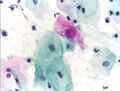

صورة مجهرية لاختبار عنق الرحم تظهر داء المشعرات . كائن المشعرات يظهر في أعلى اليمين. صبغة عنق الرحم .